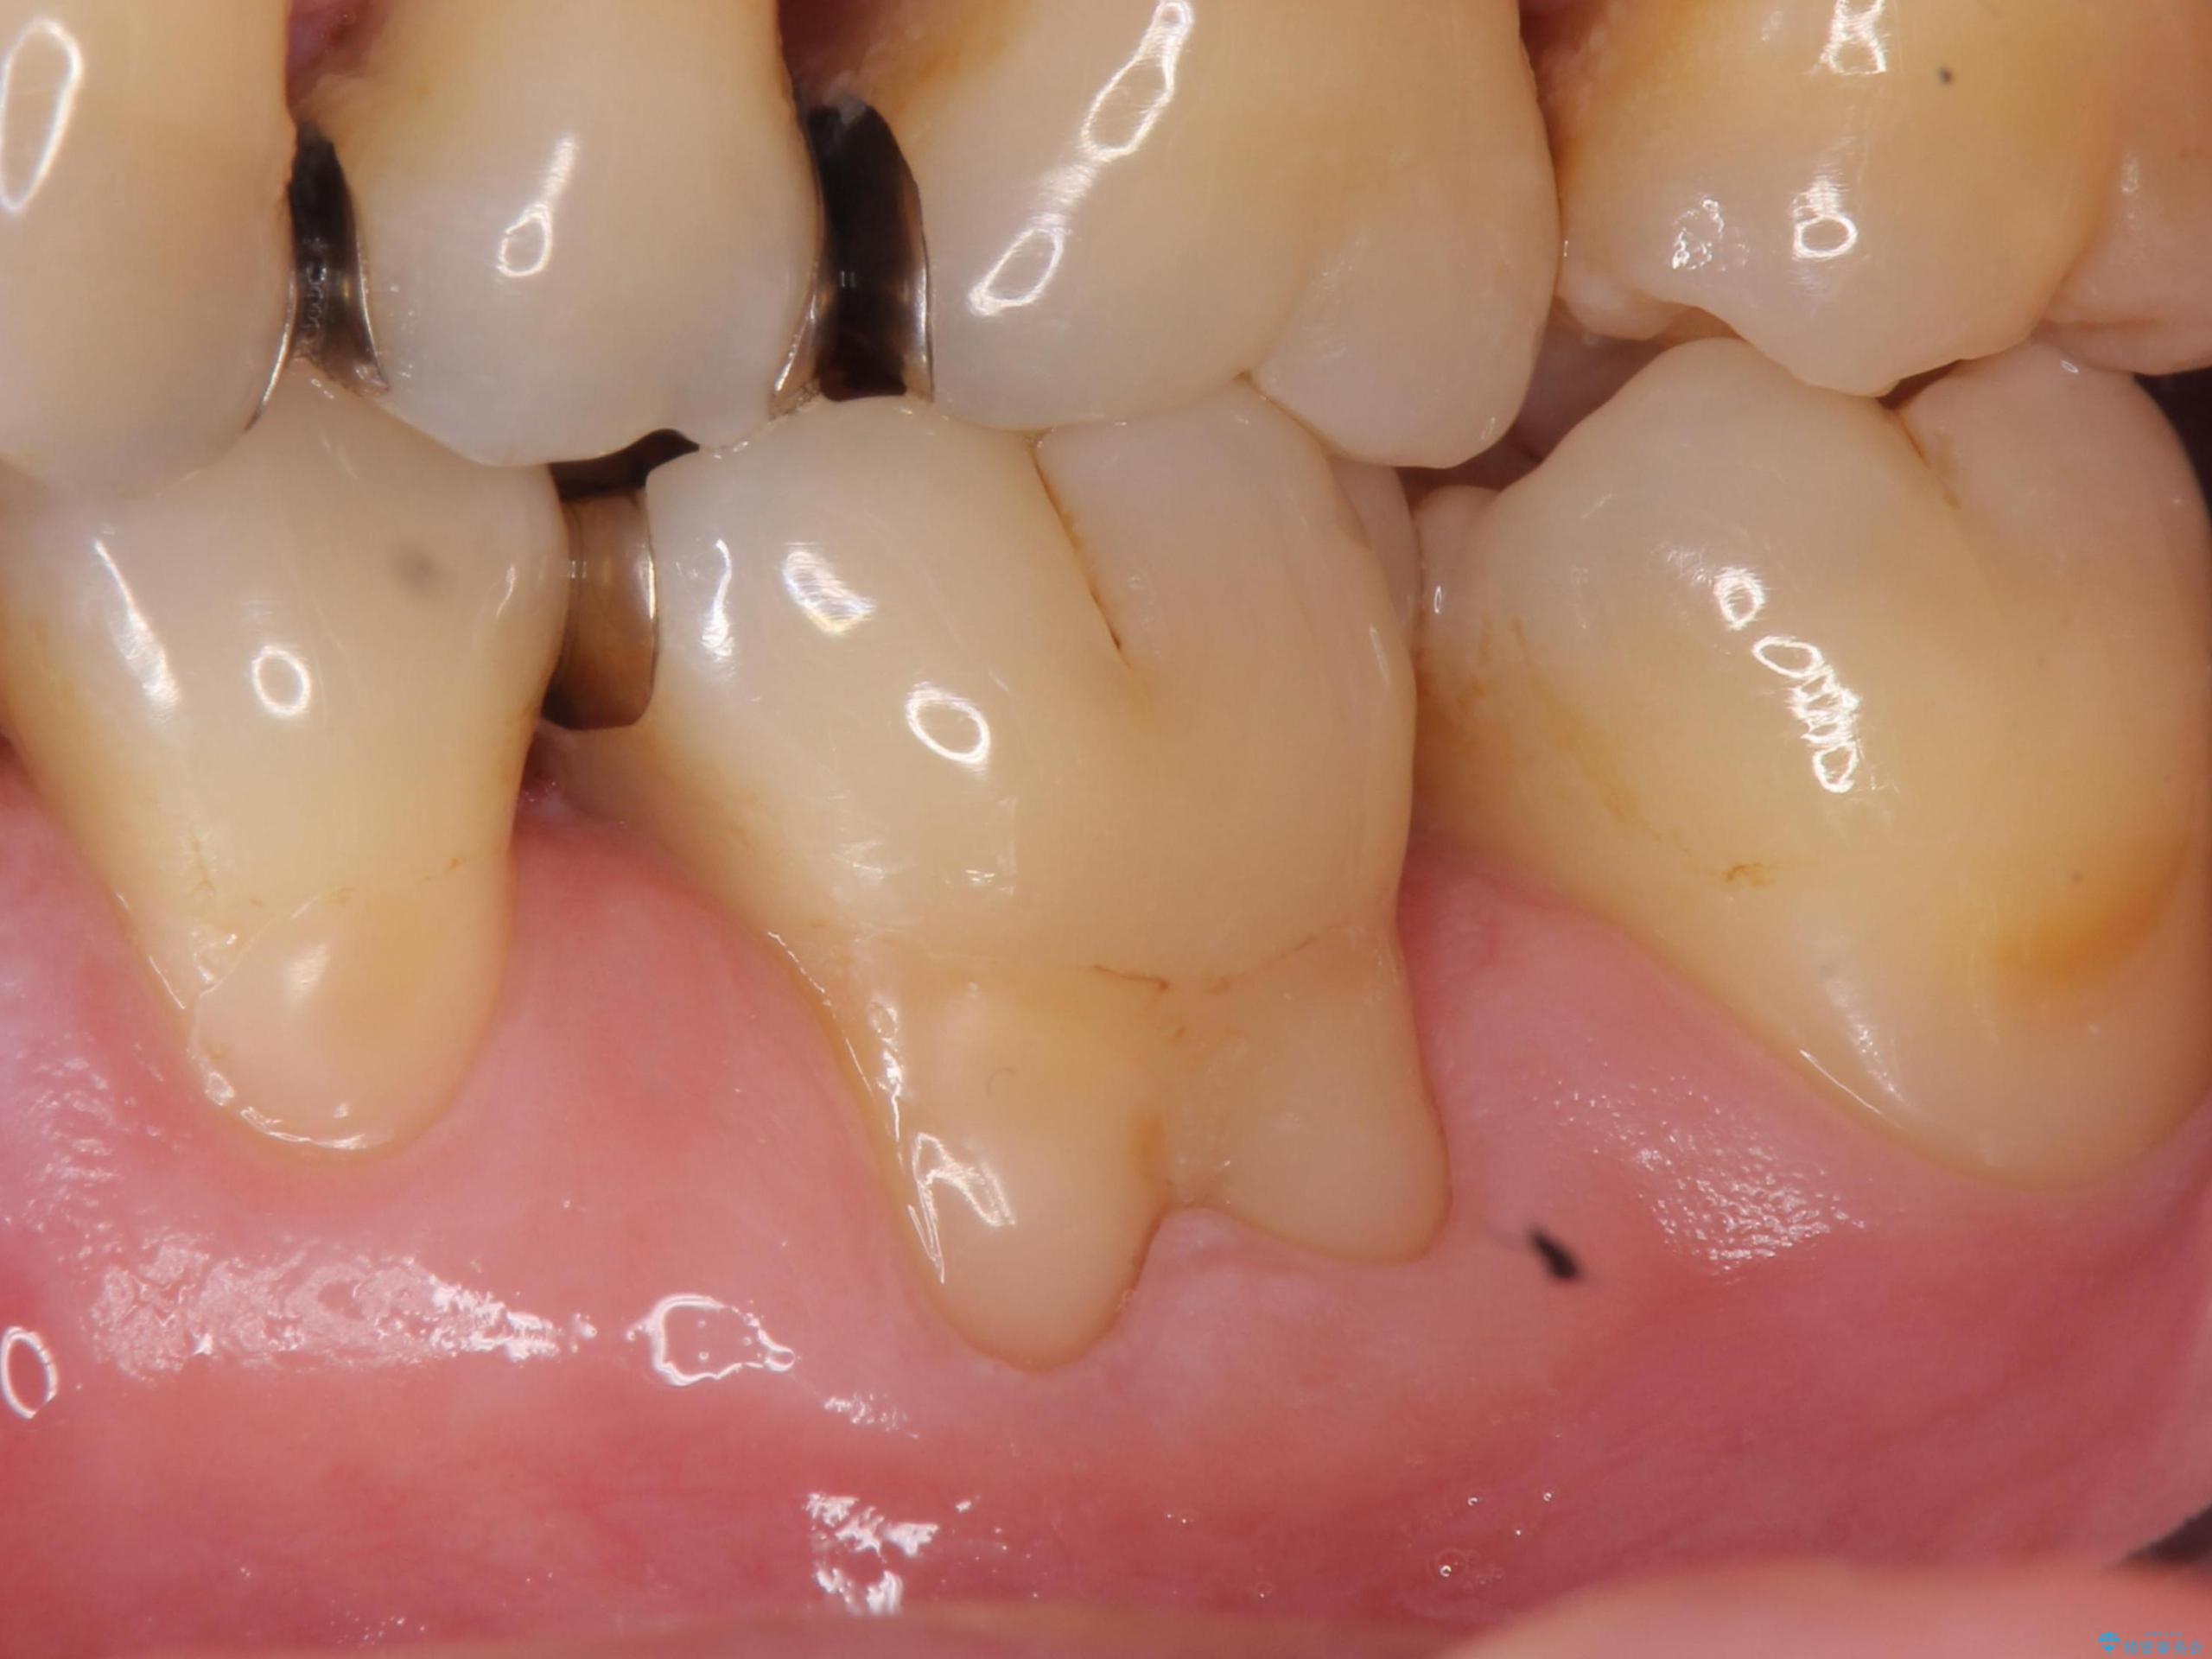

- 奥歯の歯茎が下がっていて(歯肉退縮)歯が染みるとのことで来院された患者様です。

退縮した歯茎に対して移植をすることで、しみる場所を覆う計画です。

歯根の分岐部よりも根尖側の頬側面が露出している状態でしたが、露出部位を分岐部までに抑えることができました。